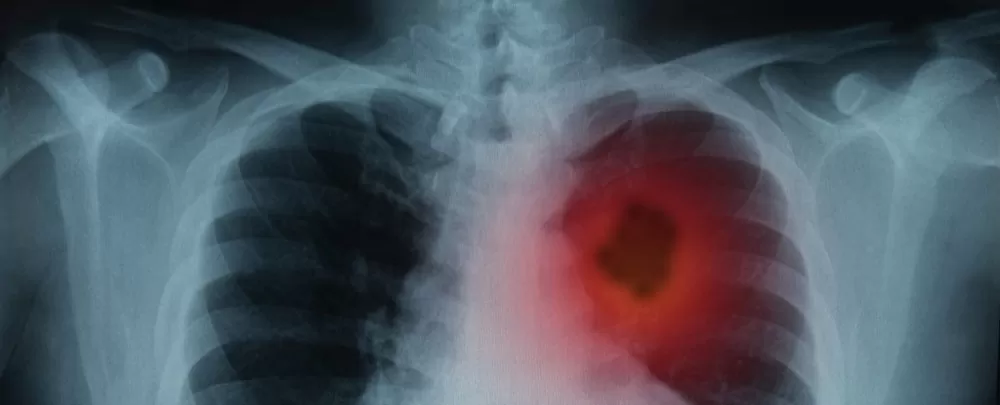

une nouvelle étude a révèle qu’un nouveau medicament contre le cancer,  agit sur le système immunitaire, semble aider à prolonger la vie des patients, atteints d’un cancer du poumon avancé, lorsqu’on l’administre en même temps que la chimiothérapie standard, . Mais comment ce médicament agit-il exactement pour aider à combattre le cancer?

L’étude, a inclus plus de 600 personnes, elle a montré que les patients, atteints d’un type commun de cancer du poumon, ayant reçu le soi-disant immunothérapie( nouveau medicament contre le cancer ); en association avec la chimiothérapie, avaient 51% moins de risques de mourir, sur une période de 10,5 mois que les patients un placebo et une chimiothérapie (groupe témoin).

poumon atteint d’un cancer de poumon

De plus, le «temps de survie sans progression» médian, ou le temps passé sans aggravation de la maladie, était de près de neuf mois dans le groupe immunothérapie, contre cinq mois dans le groupe témoin.